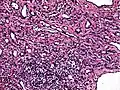

- Low power photomicrograph of an endovascular papillary angioendothelioma showing papillae with hyalinized cores

- High power view showing a vascular tumor with cuboidal endothelium lining the vessels. Few entrapped seminiferous tubules are also noted (arrow).

- Characteristic budding, hobnail-like endothelial cells visible.